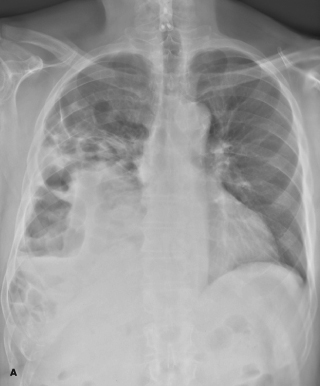

Nelson L. Turcios, MD

<p>An 18-year-old girl was referred for evaluation of “uncontrolled asthma.” She had a long-standing history of recurrent coughing, wheezing, and documented pneumonias that were treated with frequent...